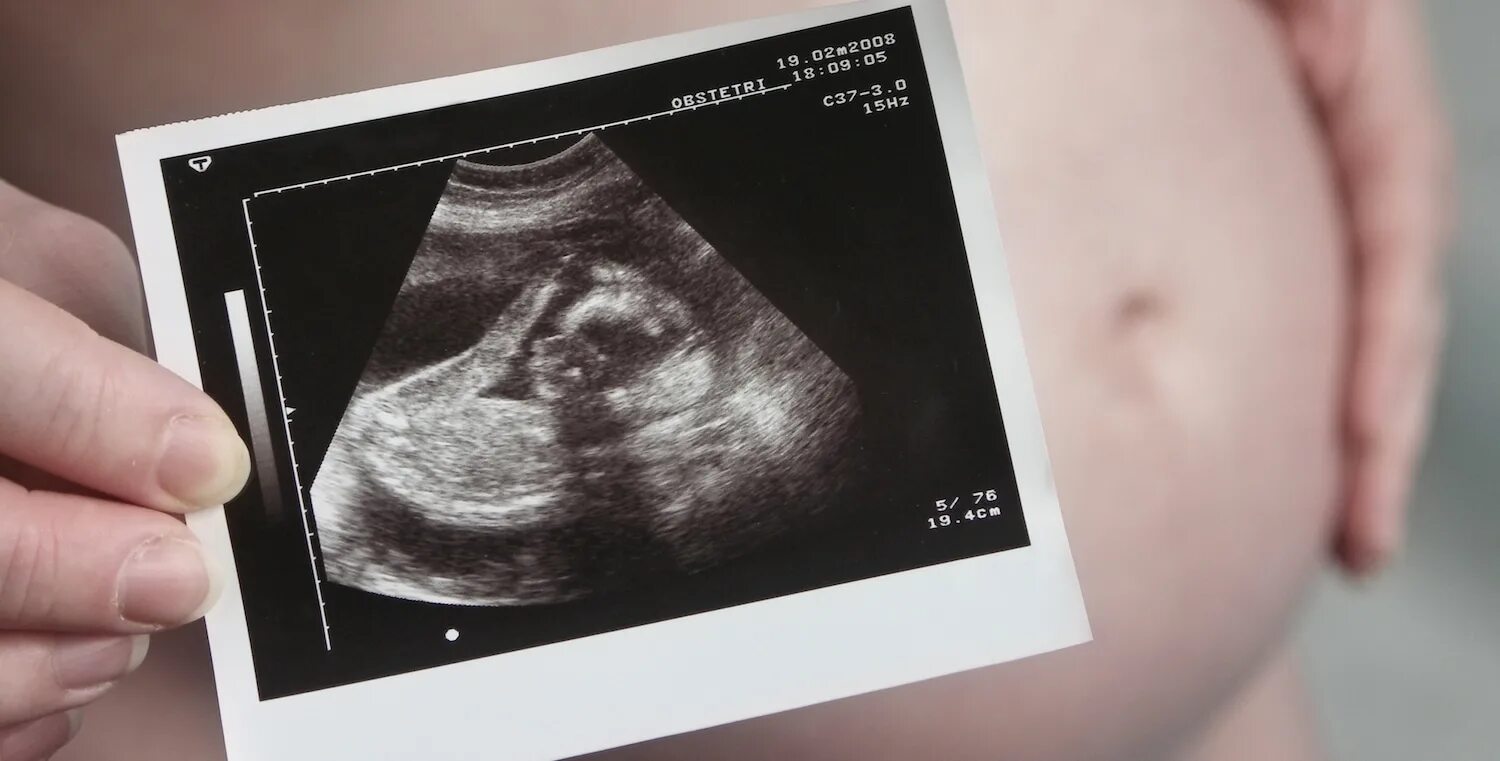

Скрининг 21 неделя